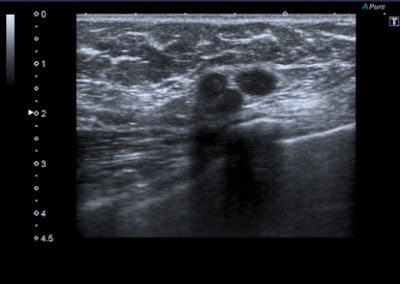

Malignant lesions usually present with features such as acoustic shadow, spicules, indented margins, hyperechogenic halo with desmoplastic reaction around the lesion, calcifications, spreading along the ducts, and significant vascularization. Cancer can also have nonspecific features such as uneven architecture and gland edema.

Tumor stiffness is a characteristic of extracellular matrix, modulated by collagen cross-linking. Malignant lesions are less prone to deformation by pressure than normal breast tissue and have a more complex elastic modulus. Softer malignant lesions, including medullary, mucinous, papillary, cystic, and some necrotic infiltrating ductal carcinomas, are uncommon.

Elastography is often used in "uncertain" lesions classified as BI-RADS 3 and 4, but it does not change medical protocol in cases of BI-RADS 1, 2, and 5 lesions. The mean elasticity score of color map was significantly higher for malignant lesions than for benign lesions (p < 0.001), usually mainly represented as blue areas in the color map.